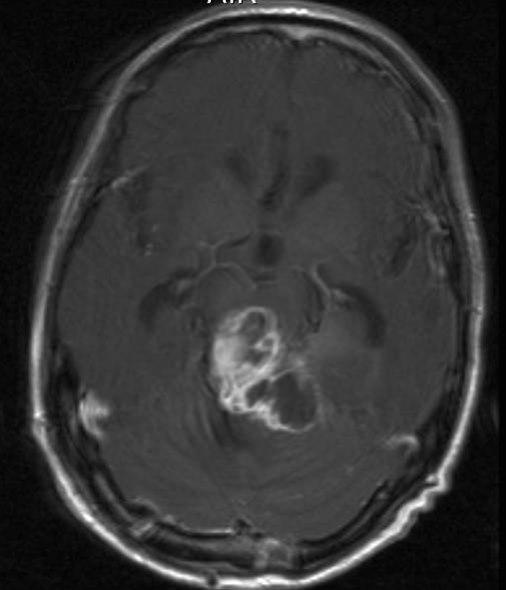

Pineoblastom, aksialt snitt

Gjengitt med tillatelse av Radiologisk avdeling, Universitetssykehuset Nord-Norge